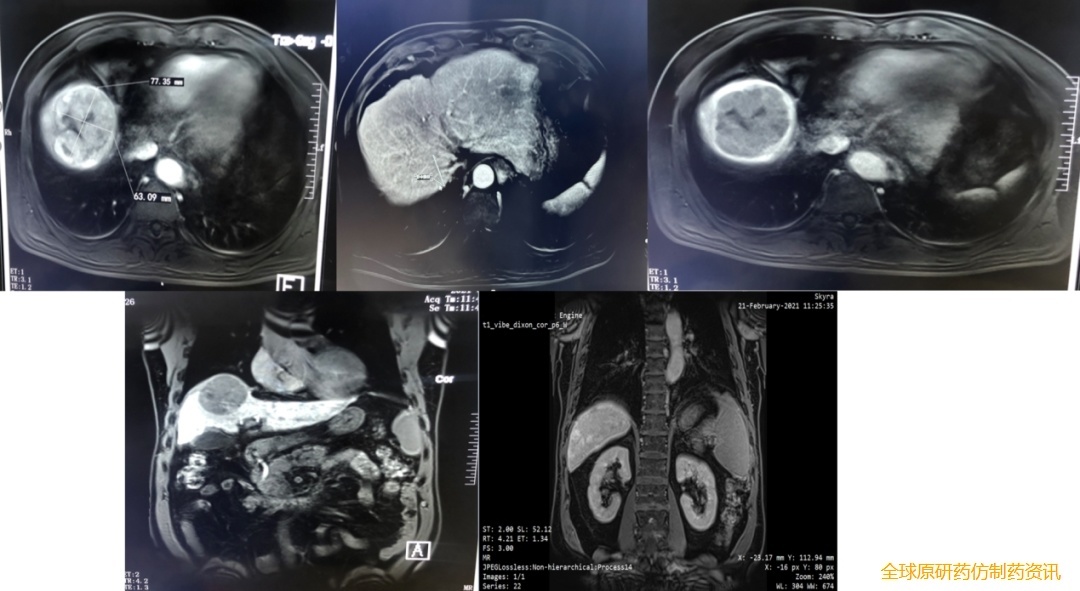

腹部MRI平扫+增强(2021.2.21):肝脏体积缩小,边缘欠光整,DWI呈稍高信号,增强扫描显示动脉期可见不均匀强化,门脉期及延迟期较前减退,肝胆特异期可见造影剂廓清呈低信号,大小约62mmx73mm。

图1 基线影像学检查